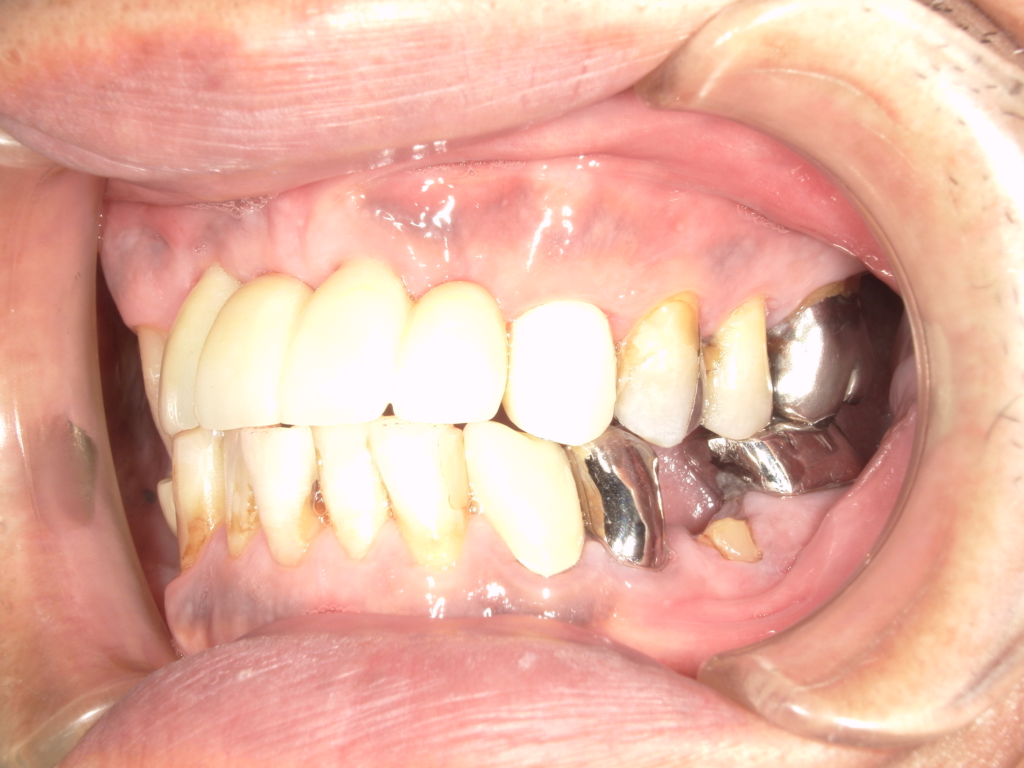

Y様インプラント実例 #44

左の上下の奥歯をインプラントで治療しています。

左下の奥歯は歯を抜くのと同時にインプラントの埋め込みを行っています。

被せものは上下、セラミックスで作っています。

治療前

治療後